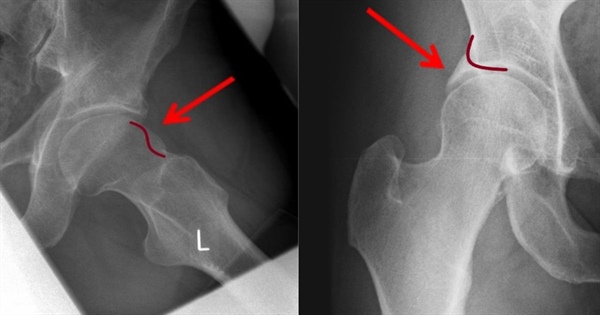

Κατάγματα Ισχίου σε Άτομα Μεγάλης Ηλικίας: Αιτίες, Συμπτώματα και Αντιμετώπιση

Στις περισσότερες περιπτώσεις, αυτά τα κατάγματα σχετίζονται με την οστεοπόρωση, την απώλεια οστικής πυκνότητας και τη γενικότερη αστάθεια λόγω της ηλικίας. Μια απλή πτώση ή ακόμα και μια απότομη κίνηση μπορεί να οδηγήσει σε σοβαρό τραυματισμό, ο οποίος απαιτεί άμεση ιατρική παρέμβαση.